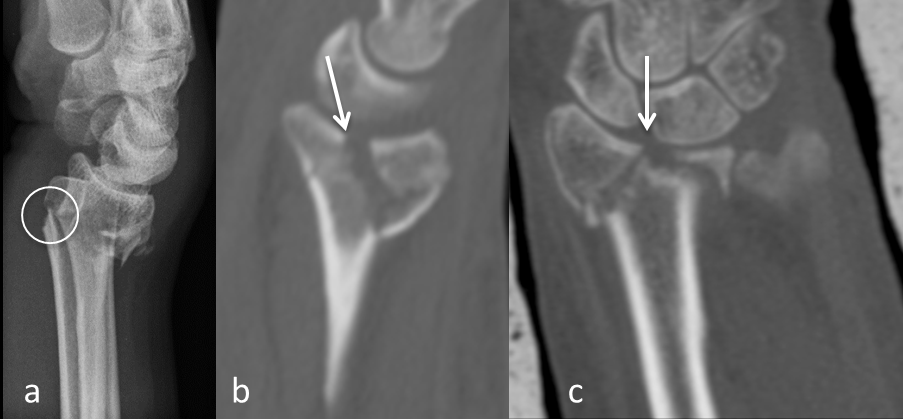

The fact that only displaced fracture parameters have been taken in account for the decision of the surgical approach led to a subgroup of fractures that had paradoxically no palmar cortex and no frontal split as these fracture parameters were not displaced (Figure 3 [Fig. 3]). These fractures did not follow the before mentioned observation. In these cases, the palmar cortex was fractured very far distally and the articular surface was impacted in the metaphysis. We observed 31 of these fractures in our collective: 7 were operated from dorsal, 16 from palmar, and 8 were fractures of the radial styloid process (type B1) that were treated percutaneously.

Figure 3: a: CT in sagittal plane showing the palmar cortex is not displaced. b: CT in frontal pane showing a sagittal split of the articular surface. c: CT in axial plane showing a sagittal split of the articular surface. Distal radius fracture (AO type C2) with a non-displaced palmar cortex (i.e. no palmar cortex) and no frontal split.

The interesting group of “neither palmar cortex nor frontal split fractures” need further evaluation (Figure 3 [Fig. 3]). These fractures are usually not grossly displaced and often amendable to conservative treatment. Their indication for surgery is mainly a dorsal tilt greater than 20 degrees. In these cases, both approaches are feasible: a palmar approach where the tilt is restored with reduction over the plate; a dorsal approach with direct reduction of the impaction. Indirect reduction in these fractures is usually not possible because the joint is impacted in the metaphysis.